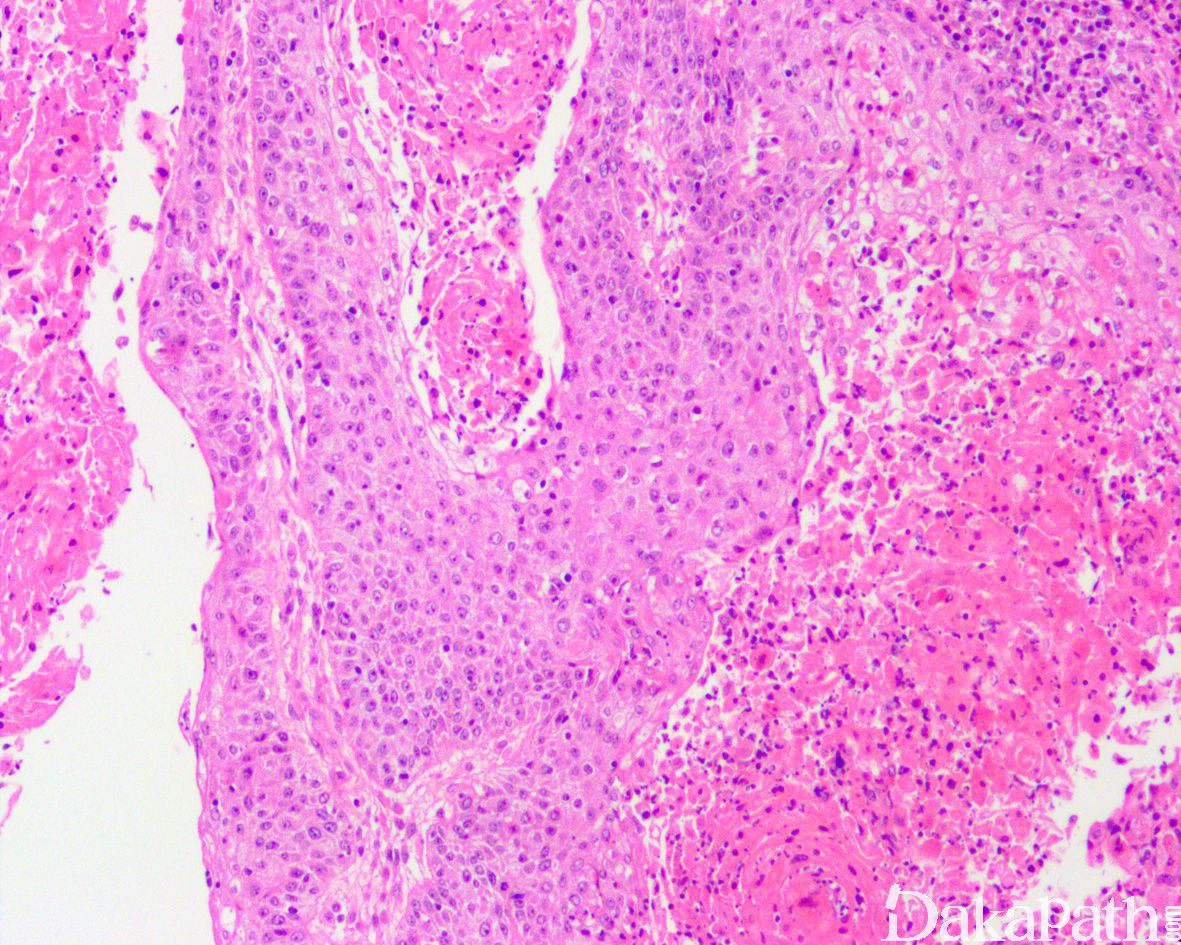

- 肿瘤在组织学上完全由具有鳞状上皮分化的癌组织构成。可以是具有角化、明显细胞间桥、轻度细胞核多形的分化好的癌细胞巢,也可以分化很差仅有局灶性鳞状分化的证据,亦可表现为基底细胞样鳞状细胞癌;约 17-62%的肿瘤表面可见鳞状上皮化生。

尿路上皮癌伴鳞状分化:至少存在局灶的浸润性尿路上皮癌成分,而按照定义,膀胱鳞状细胞癌完全由鳞状上皮成分组成。需要注意的是,低分化的鳞状细胞癌有时候在形态学上可能与高级别尿路上皮癌无法明确区分。

疣状癌:为特别高分化的鳞状细胞癌亚型,肿瘤由外生性的乳头状瘤样结构组成,细胞缺乏明显的异型性。基底为宽基的推挤状生长而非浸润性生长。